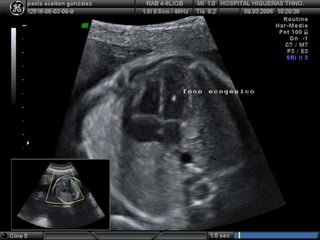

• SISTEMA VENTRICULAR: normalmente se identifican

las distintas porciones de ventric lat: cuernos frontales,

cuerpo, atrio, cuernos occipitales y cuernos inf

¿ DÓNDE MEDIR ?

PLANO PARALELO A DBP,

LIGERA% HACIA CORTICAL

• ATRIO: lo + útil para HIDROCEFALIA. Se mide en DBP,

en su interior : plexos coroideos (muy refringentes)

NORMAL: HASTA 7 mm

> 10 mm: HIDROCEFALIA